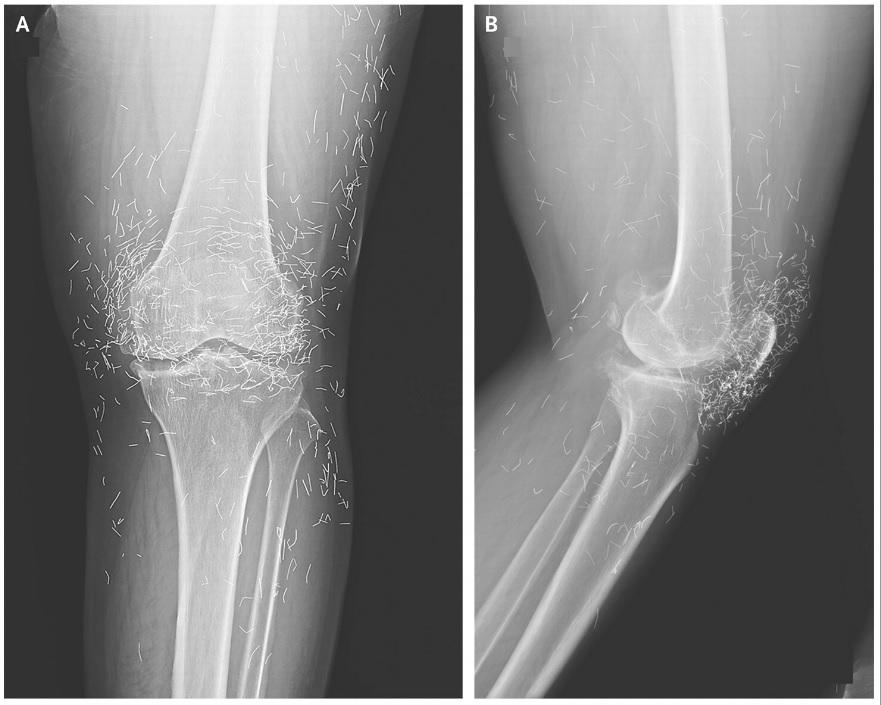

दक्षिण कोरिया: घुटने के एक्स-रे में सोने के तार

दक्षिण कोरिया की 65 साल की महिला के घुटनों में दर्द के एक्स-रे में कुछ ऐसा मिला, जो अनोखा और चौंकाने वाला था। महिला के घुटनों के एक्स-रे में ‘सोने के तार’ दिखाई दिए। यह पता चला कि उन्होंने ऑस्टियोआर्थराइटिस के इलाज के लिए एक्यूपंक्चर का सहारा लिया था, जिसमें सोने के तार जान-बूझकर टिश्यू … Read more